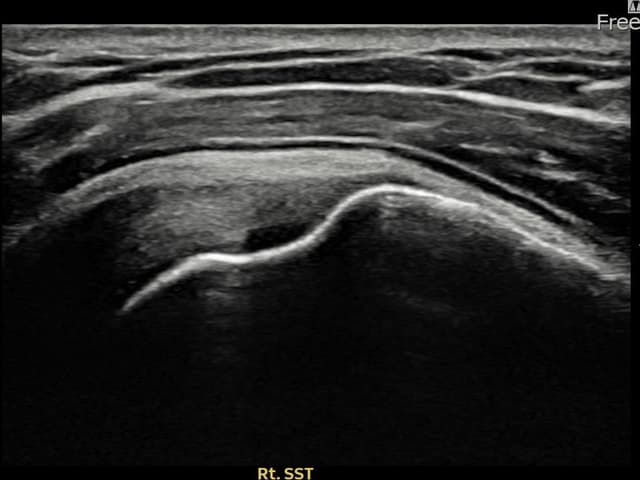

実際の患者様の施術前後の超音波画像。

手術なしで実現できる回復をご確認ください。

[経過期間: 23.10.23~24.01.04]

[縫縮術] 超音波検査にて左 棘上筋腱 関節面側部分断裂(8mm × 3mm (腱厚の約33%欠損))を確認。縫縮術施行後、腱の連続性が回復し、日常生活に復帰されました。